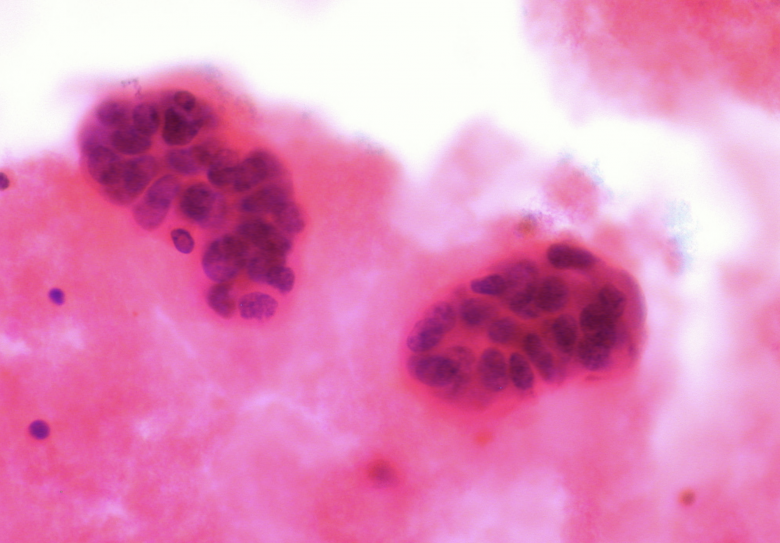

Cervical cancer

“Cervical cancer is nearly always caused by infection with human papillomavirus (HPV).

“There are usually no signs or symptoms of early cervical cancer but it can be detected early with regular check-ups. Signs and symptoms of cervical cancer include vaginal bleeding and pelvic pain.

“Tests that examine the cervix are used to detect (find) and diagnose cervical cancer. Certain factors affect prognosis (chance of recovery) and treatment options.”

Image Credit: National Cancer Institute / Wikimedia Commons.